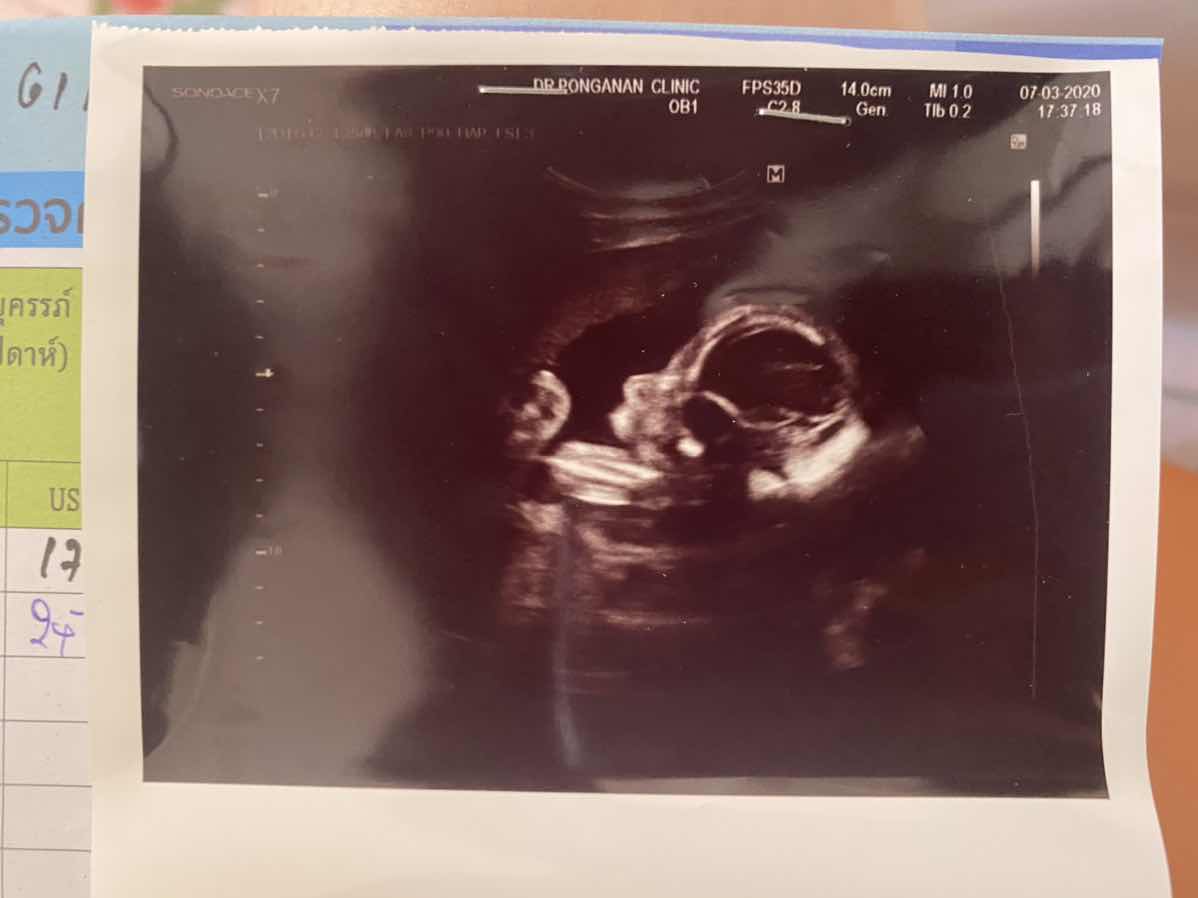

บ้านนี้ 11 สัปดาห์ จมูกแหลมๆค่ะ55